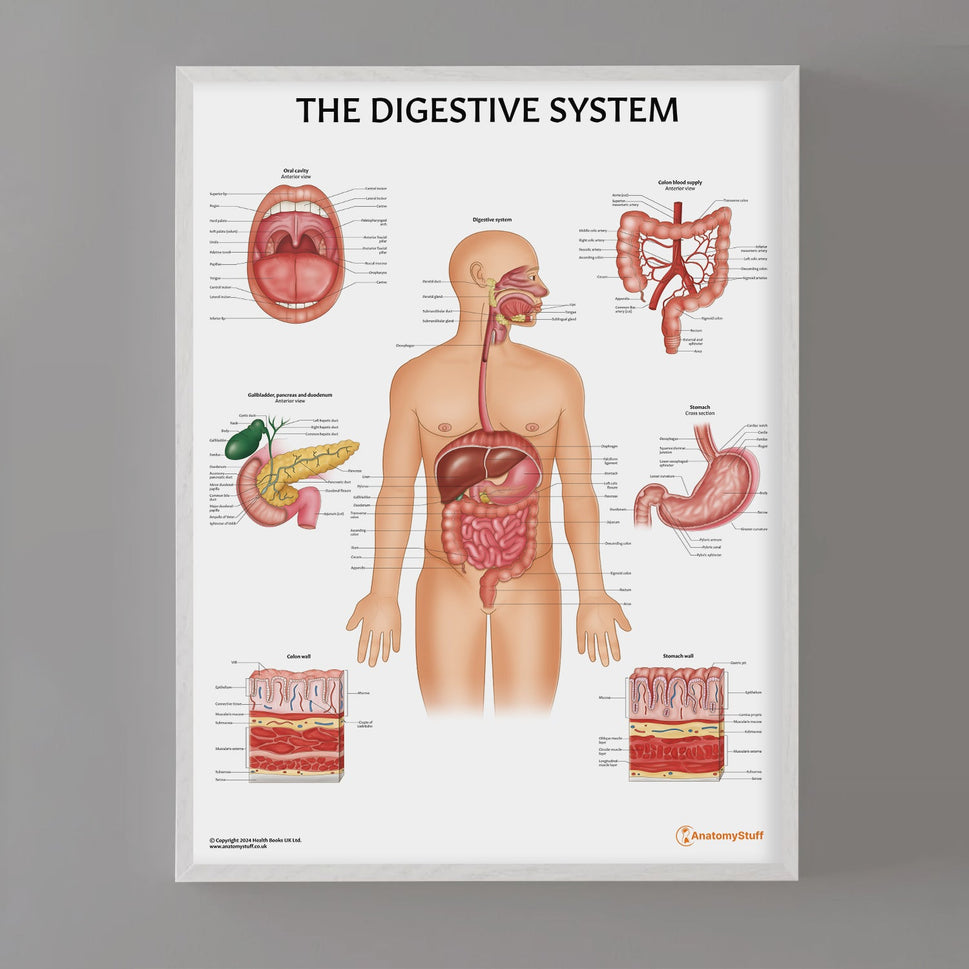

Enhance medical education with our collection of digestive system anatomical models including the stomach, liver, gallbladder, pancreas & colon models. Discover the anatomy of healthy organs as well as common gastrointestinal diseases such as stomach ulcers, gallstones and liver cirrhosis. Our digestive system anatomy posters are ideal for study and patient education.

At AnatomyStuff we stock a diverse range of digestive system anatomical models to suit your training needs. From budget models and affordable medical education posters to highly advanced 3D printed bowel models, you can transform medical training and patient education. As well as our own exclusive collection, we are proud resellers of 3B Scientific, Anatomy Lab, Denoyer-Geppert Science Company, ESP Models, Erler Zimmer and GPI Anatomicals. Explore our exclusive collection of digestive system anatomy charts, posters, fine art prints and digital anatomy study guides. Discover the anatomy of key organs like the liver, stomach, pancreas and bowel as well as the pathophysiology of common conditions like peptic ulcer disease, coeliac disease, IBD and much more. We have anatomy posters suitable for school children all the way up to medical degree level. From a liver anatomy poster to a digital study guide all about common GI disorders, find exactly what you need right here to enhance medical training and patient education.